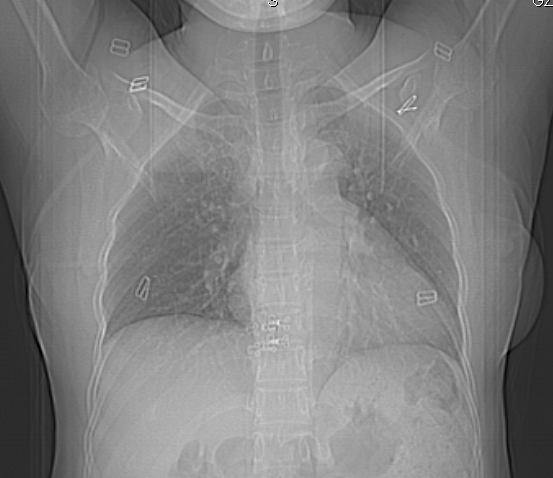

标题: CT25227:背部疼痛伴双侧胸壁痛2月,食欲差。 [打印本页]

标题: CT25227:背部疼痛伴双侧胸壁痛2月,食欲差。

肺结核并胸椎结核?请各位高手指教。

用椎体的条件来扫胸椎呀!考虑1左侧胸膜小结节形成2椎体结核并冷脓肿形成

左肺结核灶,胸椎结核并冷脓肿。

左肺结核灶,胸椎结核并冷脓肿